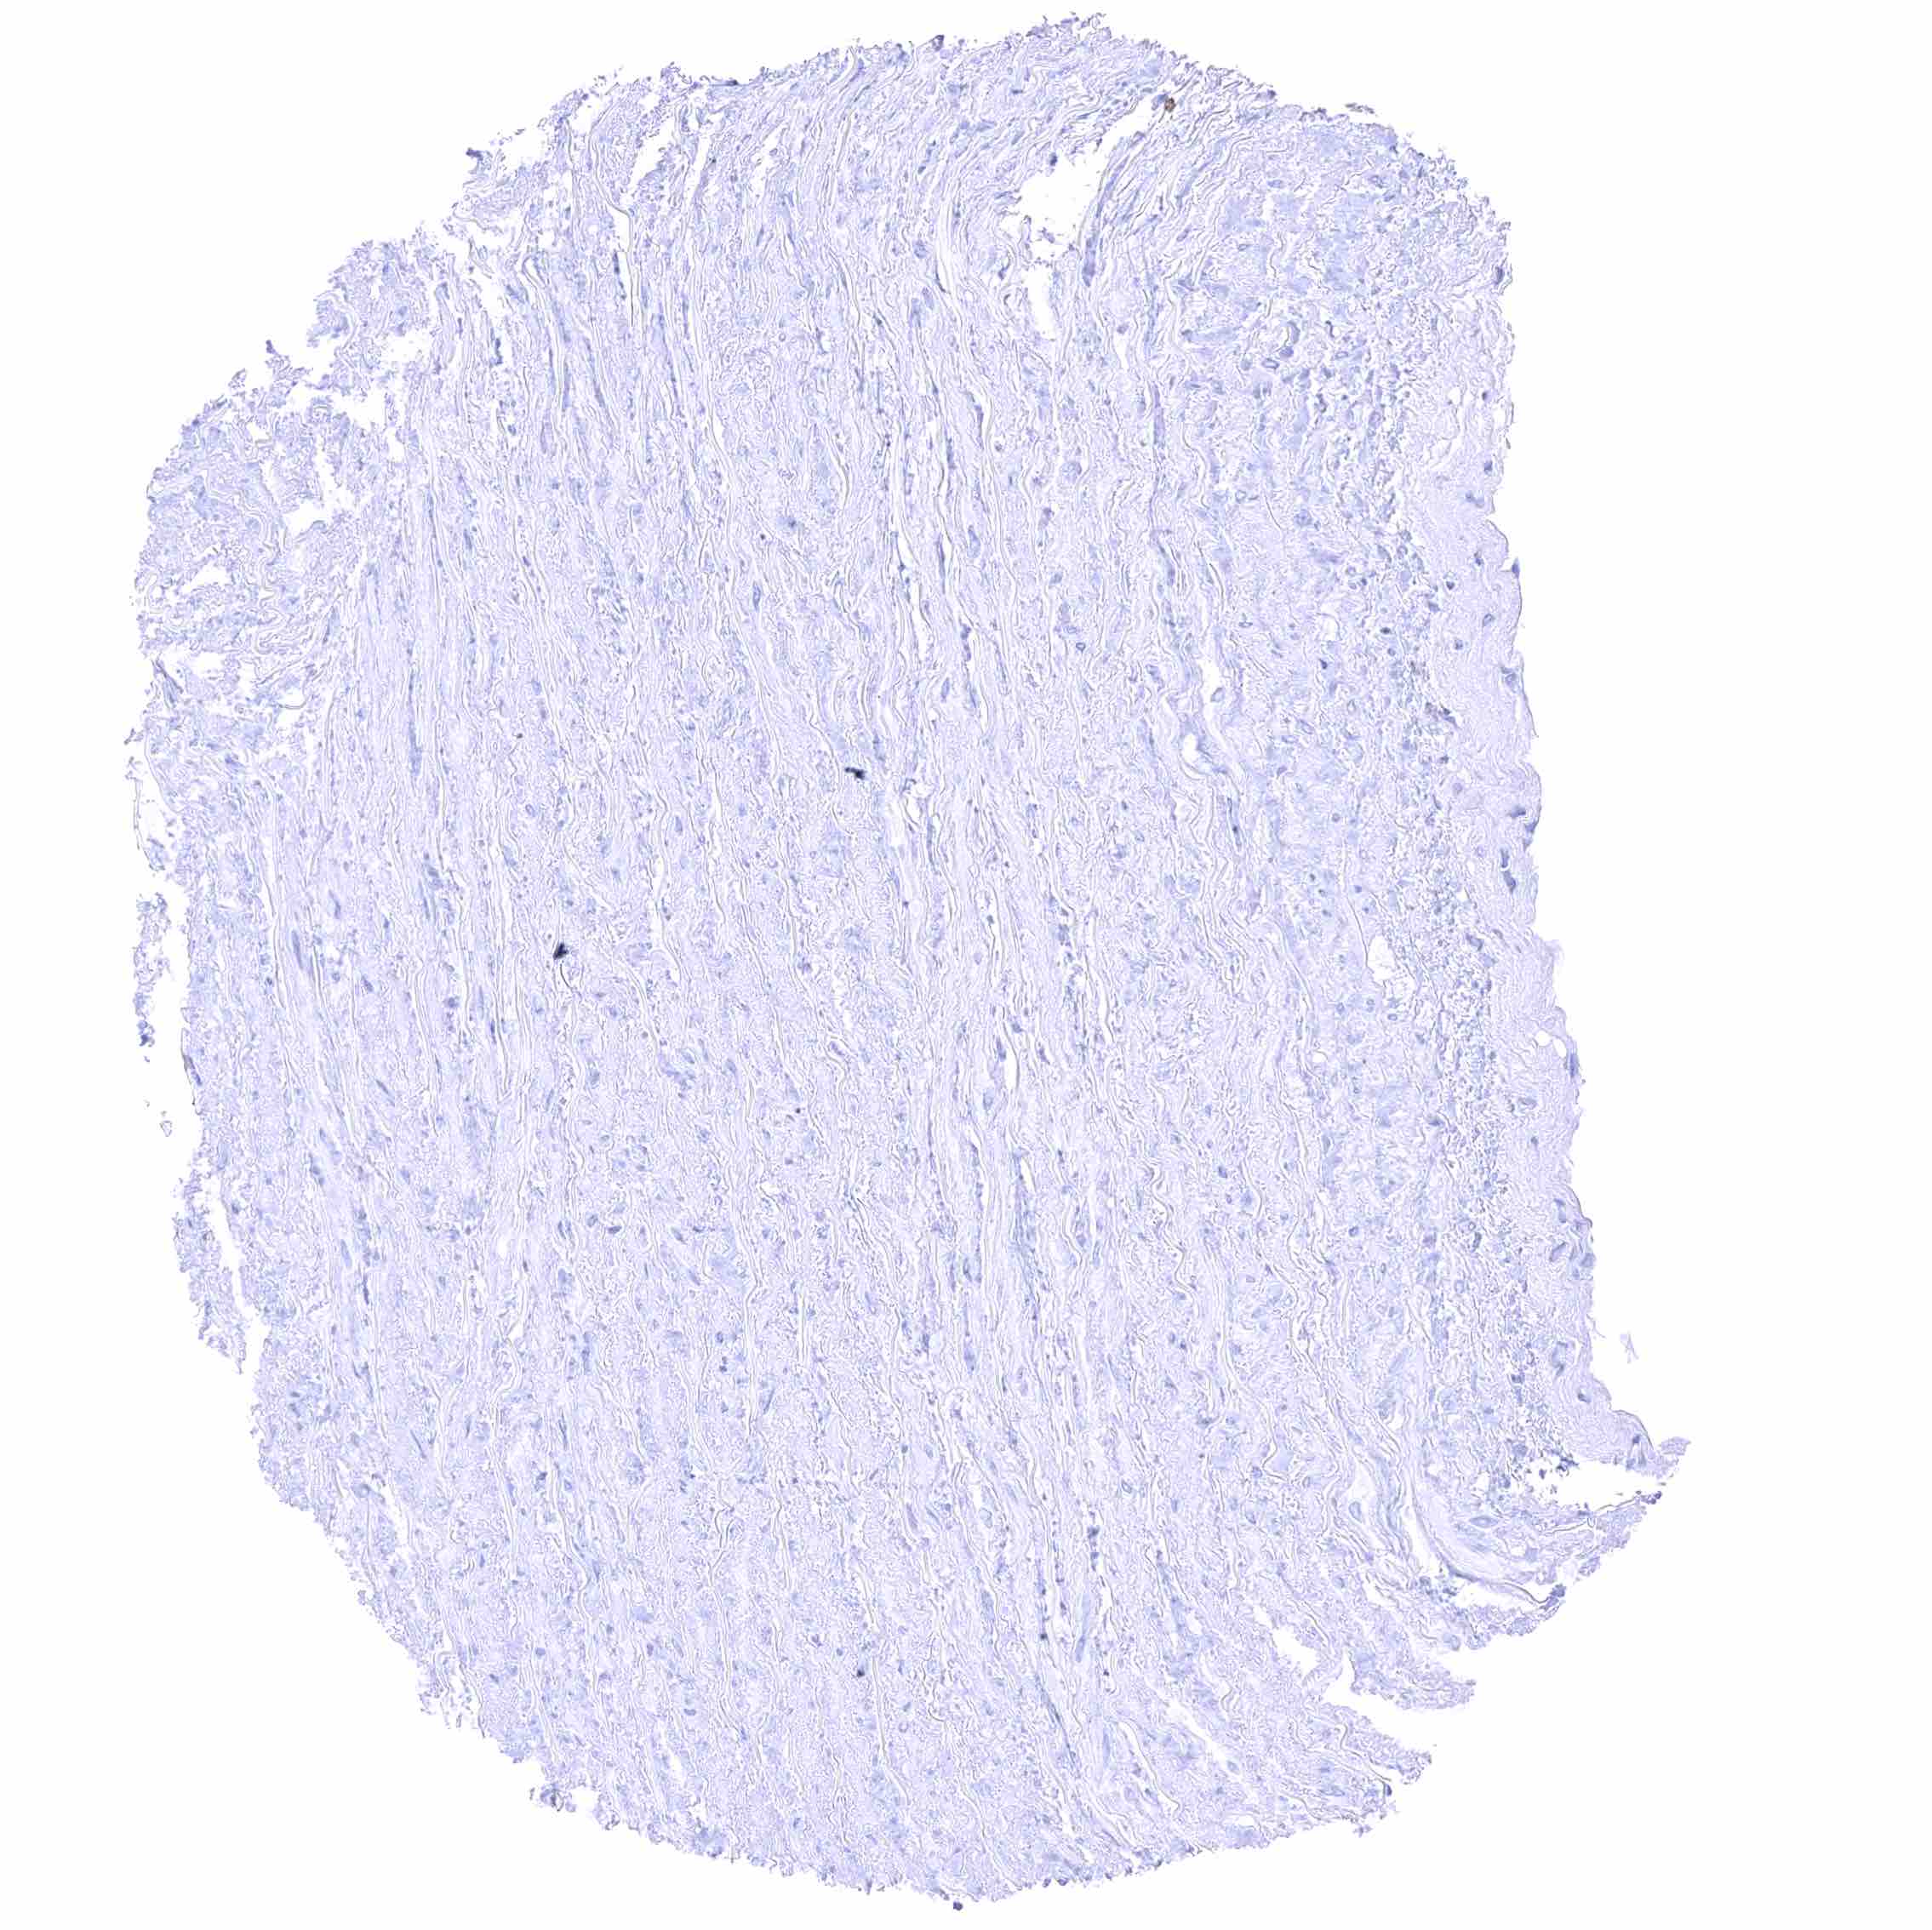

Uterus, myometrium